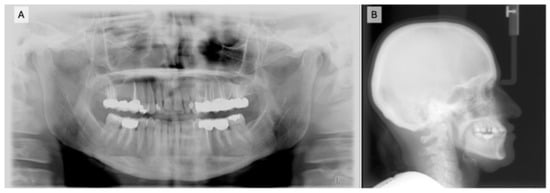

Three months later, the patient was scanned for Invisalign® treatment (Align Technology, Santa Clara, CA, USA) (Figure 9A–E).

Figure 9.

Intraoral scans for clear aligner: (A) right occlusion; (B) front occlusion; (C) left occlusion; (D) maxillary occlusion; (E) mandibular occlusion.